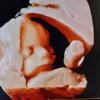

@miriek.elete: Válasz @Mátyás-Sepovics Anett részére #pcos #nőgyógyász #fyp